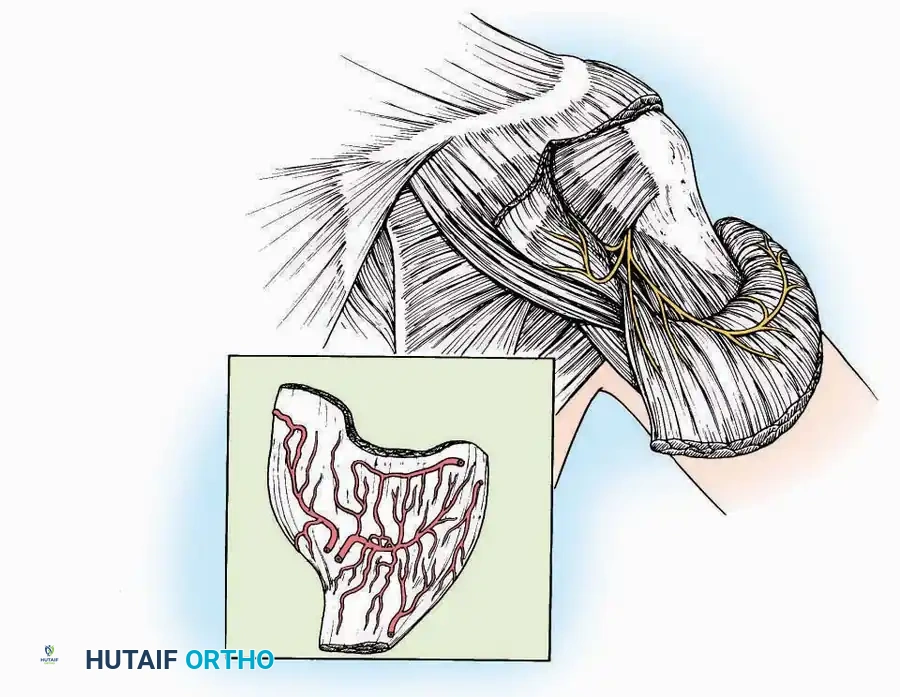

Approaches to the Metatarsophalangeal (MTP) Joint of the Great Toe

The first MTP joint is the epicenter of forefoot reconstructive surgery. Exposure can be achieved via medial or dorsomedial trajectories.

Medial Approach

Indications: Hallux valgus correction (bunionectomy), first MTP arthrodesis, or cheilectomy.

Surgical Technique:

* Incision: Make a curved incision 5 cm long on the medial aspect of the joint. Begin just proximal to the IP joint, curve it over the dorsum of the MTP joint (medial to the extensor hallucis longus [EHL] tendon), and terminate on the medial aspect of the first metatarsal 2.5 cm proximal to the joint.

* Superficial Dissection: As the deep fascia is incised, identify and laterally retract the medial branch of the first dorsal metatarsal artery and the medial branch of the dorsomedial nerve (a terminal branch of the superficial peroneal nerve).

* Deep Dissection: Dissect the fascia from the dorsum down to the bursa overlying the medial eminence of the metatarsal head.

* Capsulotomy: Make a curved incision through the bursa and joint capsule. Begin dorsomedially, continue proximally dorsal to the metatarsal head, sweep plantarward, and end distally on the medioplantar aspect of the joint. This creates an elliptical, racquet-shaped flap attached at the base of the proximal phalanx.

⚠️ Surgical Pitfall

While distal reflection of this racquet flap provides ample exposure of the first MTP joint, the extensive subfascial undermining required can compromise the vascularity of the skin flap, leading to delayed healing or necrosis. Consequently, the dorsomedial approach is often preferred in modern practice.

Dorsomedial Approach

Indications: Preferred approach for primary and revision first MTP arthroplasty, arthrodesis, and complex bunion corrections due to superior angiosome preservation.

Surgical Technique:

* Incision: Begin just proximal to the IP joint and extend proximally for 5 cm, running parallel and strictly medial to the EHL tendon.

* Exposure: Divide the superficial fascia. Identify and retract the EHL tendon laterally.

* Capsulotomy: The capsule can be incised longitudinally in the exact plane of the skin incision, allowing for subperiosteal elevation of the capsule medially and laterally, preserving the vascular supply to the medial skin flap.